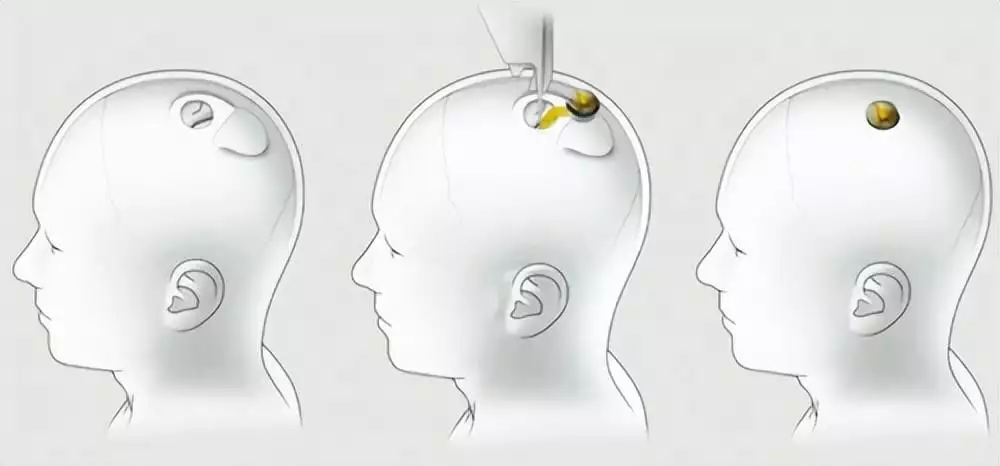

关于马斯克的脑机接口,之前和大家介绍过几次了。Neuralink是他在2016年搞起来的,简单理解的话就是在大脑植入芯片,然后实现用「意念」控制电子设备,更远一些的目标是能够治愈瘫痪等疾病。

而Noland Arbaugh就是Neuralink的第一位人类志愿者,根据他的说法,手术很简单,一个小时后就可以出医院了,目前没有后遗症,并在直播中透露了不少相关信息。